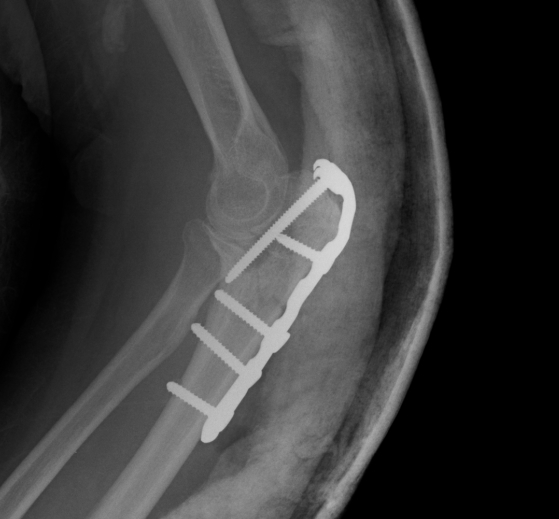

ORIF with olecranon plate

Indication

Fracture distal to center of rotation of elbow / trochlea

Technique

Lateral decubitus with tourniquet

- curvilinear incision to avoid prominence of olecranon

- identify and protect ulna nerve

- reduce fracture with arm in extension

- ensure articular congruity

- use anatomical precontoured plate

- may want to split distal triceps to reduce proximal plate prominence